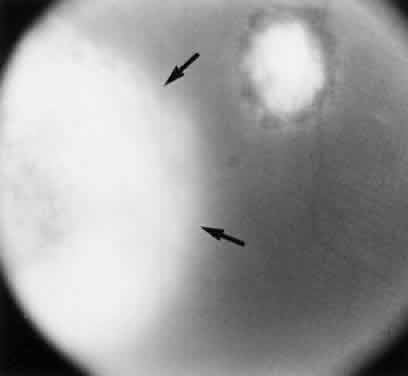

Bradyzoites are slowly metabolizing organisms found in cysts formed within the tissue of the infected host. The size of the Toxoplasma cyst varies, depending on the number of organisms that have multiplied within it. The cyst may reach more than 100 μm in diameter and may contain from 50 to 3000 organisms. The cyst wall is strongly argyrophilic and periodic acid-Schiff positive. It contains constituents that are derived from both the parasite and the host tissue. Constituent from the host tissue compose the outer part of the cyst, whereas those derived from the parasite are in the inner part of the cyst wall. Toxoplasmosis may be found in the inner layers of the retina after episodes of acute retinochoroiditis. The cyst may stay in the retinal tissue for years without showing any signs of invasiveness. Considering that the tissue cyst incorporates elements derived from the host into its outer wall, it is easily tolerated by the host, and no inflammatory reaction is seen around it (Fig. 2). It may remain for years in certain tissues, such as the eye or muscles, without provoking any inflammatory reactions. The bradyzoite inside the cyst derives its nutrition from the slow diffusion of substances through the cyst wall. The number of organisms increases within the cyst in the retina, and once the cyst wall breaks down by mechanical stretching, the bradyzoites escape, convert into tachyzoites, and invade contiguous cells. This process may lead to recurrence of retinitis. Certain immunologic mechanisms of the host may influence the organisms significantly. Immunosuppression coinciding with the rupture of the cyst and release of bradyzoites allows the organisms to become tachyzoites and proliferate in host tissue without restriction. The cyst of the Toxoplasma organism appears to be a defensive stage in its life cycle. The resistance of toxoplasmosis within chronically infected tissues of animals may lead to transmission of the disease by the ingestion of undercooked meat, including mutton, beef, pork, and chicken. Tissue cysts can develop within any organ and are commonly found in infected tissues of brain, eye, heart, skeletal muscles, and lymph nodes. Rupture of tissue cysts causes reactivation of the systemic toxoplasmosis in immune deficiency states, leading to dissemination of Toxoplasma organisms to other organs.

Fig. 2. Toxoplasma bradyzoites inside cysts of tissue sections in chronically infected rabbit's retina (arrows). The animal was killed 6 months after acute Toxoplasma retinochoroiditis after suprachoroidal injection of 1000 organisms (Beverley strain). There was no clinical evidence of inflammation at the time of killing. (H & E, × 400)